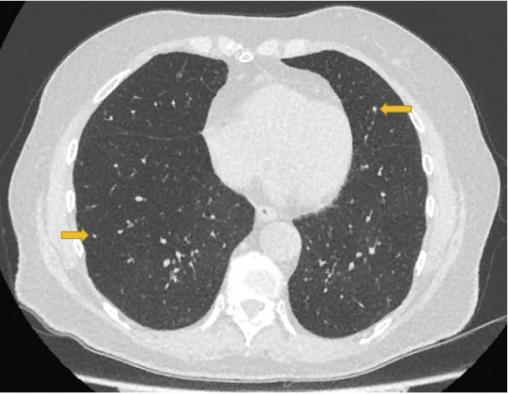

Christiane, 75 ans, consulte pour une toux invalidante, associée à une dyspnée d’effort et des sifflements. Un diagnostic d’asthme tardif a été fait à l’âge de 47 ans, traité par fluticasone à forte dose (1 000 µg/j), salmétérol et montélukast. Malgré le traitement, la toux persiste et la dyspnée s’aggrave progressivement, entraînant une limitation importante dans sa vie quotidienne. Les épreuves fonctionnelles respiratoires objectivent un trouble ventilatoire obstructif non réversible sévère (VEMS 780 ml, soit 36 %, VEMS/CV 40 %) avec une distension thoracique (volume résiduel 198 %). Le scanner thoracique (figure ) révèle des micronodules diffus (flèches jaunes ) et un aspect en mosaïque évoquant une bronchiolite. Après biopsie pulmonaire chirurgicale, l’examen anatomopathologique pose le diagnostic d’hyperplasie neuroendocrine pulmonaire diffuse idiopathique (DIPNECH).

Le scanner thoracique est l’examen clé pour redresser le diagnostic : il montre des micronodules diffus, ainsi qu’un aspect en mosaïque du parenchyme pulmonaire avec trappage aérien, évoquant une bronchiolite constrictive. Une confirmation histologique par biopsies transbronchiques ou biopsie pulmonaire chirurgicale est indispensable. Elle montre la prolifération des cellules neuroendocrines dans l’épithélium des petites voies aériennes (tumorlets)1.

Des micronodules pulmonaires diffus chez une femme ayant une toux chronique doivent faire évoquer le diagnostic de DIPNECH. Par ailleurs, rappelons qu’absence d’amélioration sous corticoïdes inhalés à fortes doses, aggravation du trouble ventilatoire obstructif et toux sèche isolée sont des éléments qui doivent remettre en cause le diagnostic d’asthme et faire pratiquer un scanner thoracique.